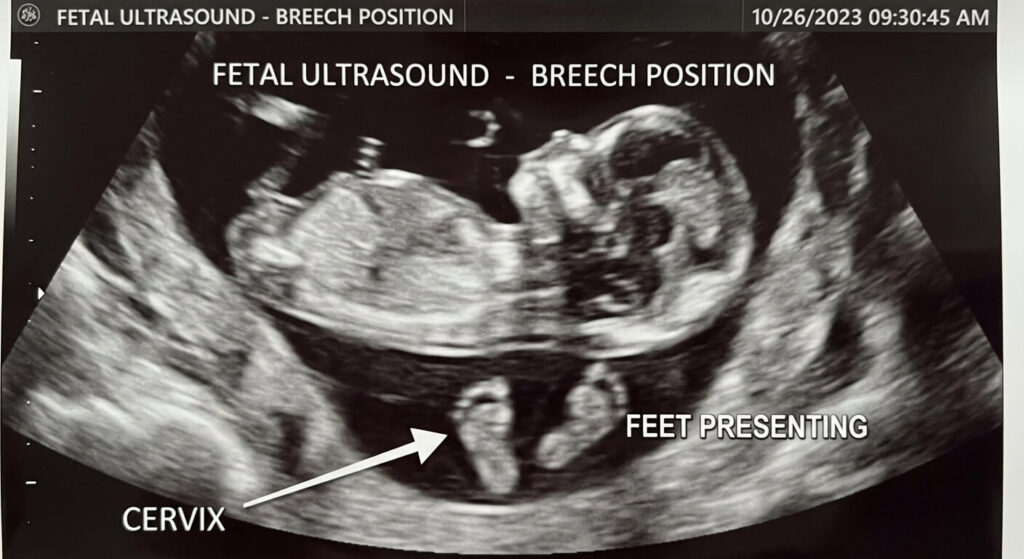

Contrairement à la fin de la grossesse où le bébé est calé la tête en bas, le fœtus de 5 mois effectue des roulades permanentes. S’il se place en présentation podalique (en siège, c’est-à-dire les fesses ou les pieds vers le bas), la cible de ses extensions de jambes devient le pôle inférieur de l’utérus. Le col de l’utérus et la région vaginale sont tapissés de milliers de terminaisons nerveuses. Lorsque le talon du fœtus heurte cette zone, la résonance neurologique est immédiate. La mère perçoit un picotement vif, une pointe douloureuse ou une pesanteur fulgurante sur le plancher pelvien, sans qu’aucun dommage anatomique n’ait lieu.